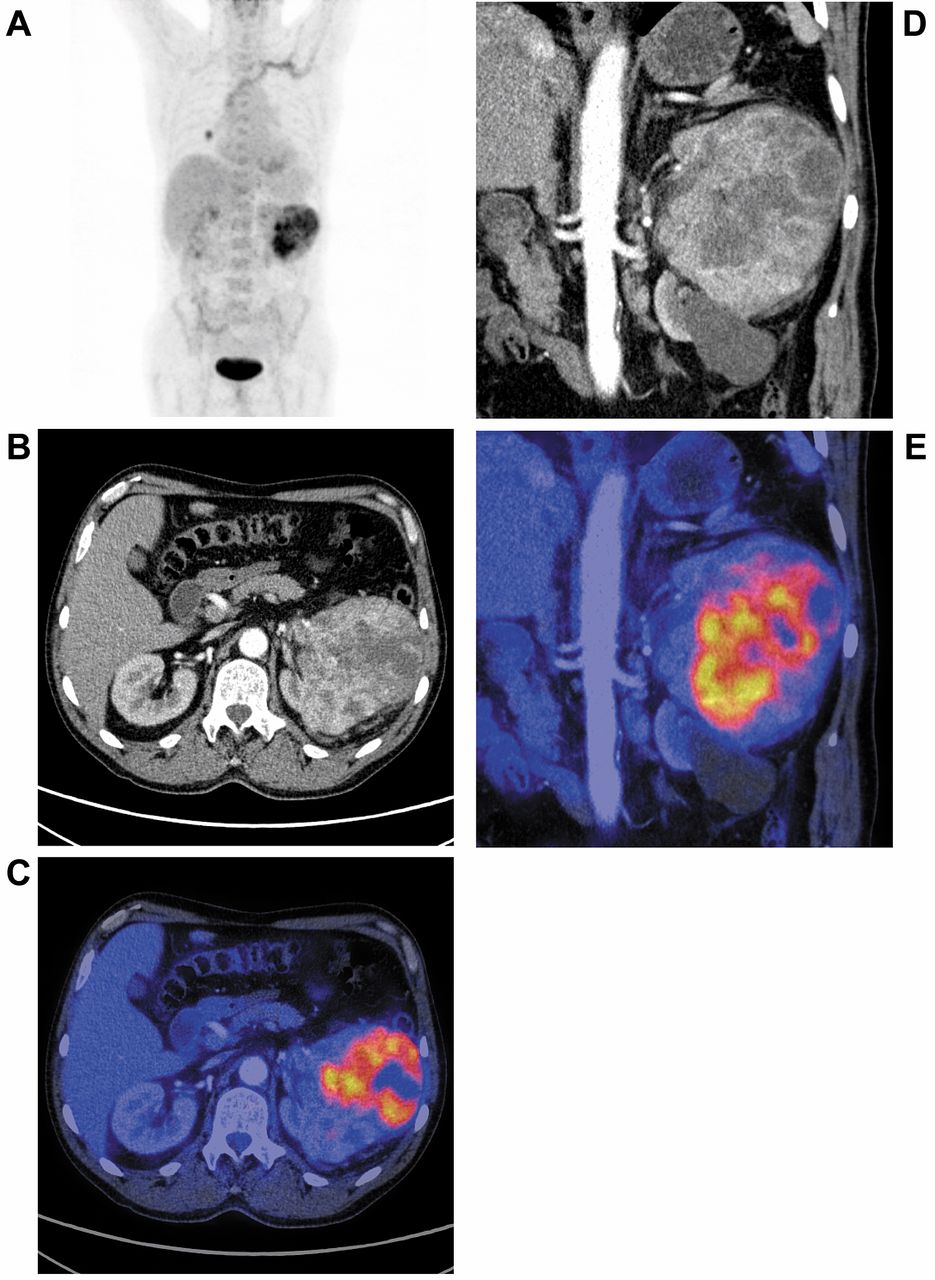

![[89Zr]Zr-girentuximab for PET–CT imaging of clear-cell renal cell ...](https://www.thelancet.com/cms/10.1016/S1470-2045(24)00402-9/asset/700721d8-bd15-46c0-a967-f0daeac9b4ac/main.assets/gr2b_lrg.jpg)